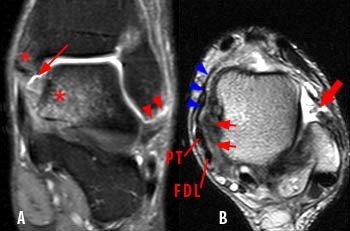

- MRI (Gold Standard): Detects soft tissue injuries, ligament tears, tendonitis, and arthritis.

The proton density-weighted fat-suppressed coronal image of the ankle (A) demonstrates partial avulsion of the anterior talofibular ligament at the distal fibula (arrowheads). The axial T2-weighted image (B)demonstrates a complete tear of the anterior talofibular ligament (thick arrow). Bone bruises are seen in the medial talus and medial malleolus (asterisks) resulting from impaction associated with a severe inversion injury